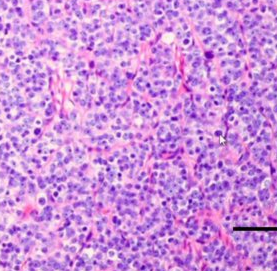

What Gleason Grade?

Grade 4